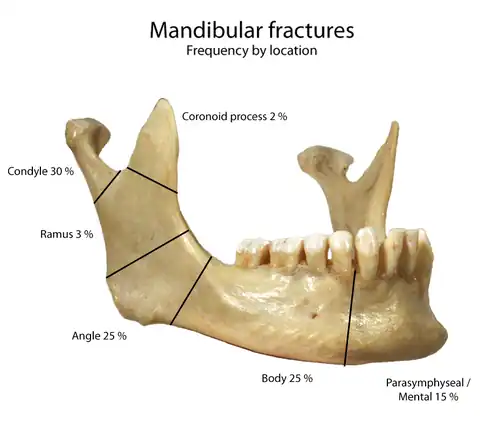

Fractures

Since the articular disk prevents the mandible from moving posteriorly, the condylar neck is often subject to fracturing when the jaw suffers a blow.[1]

Frequency of mandibular fractures by location.

Frequency of mandibular fractures by location.